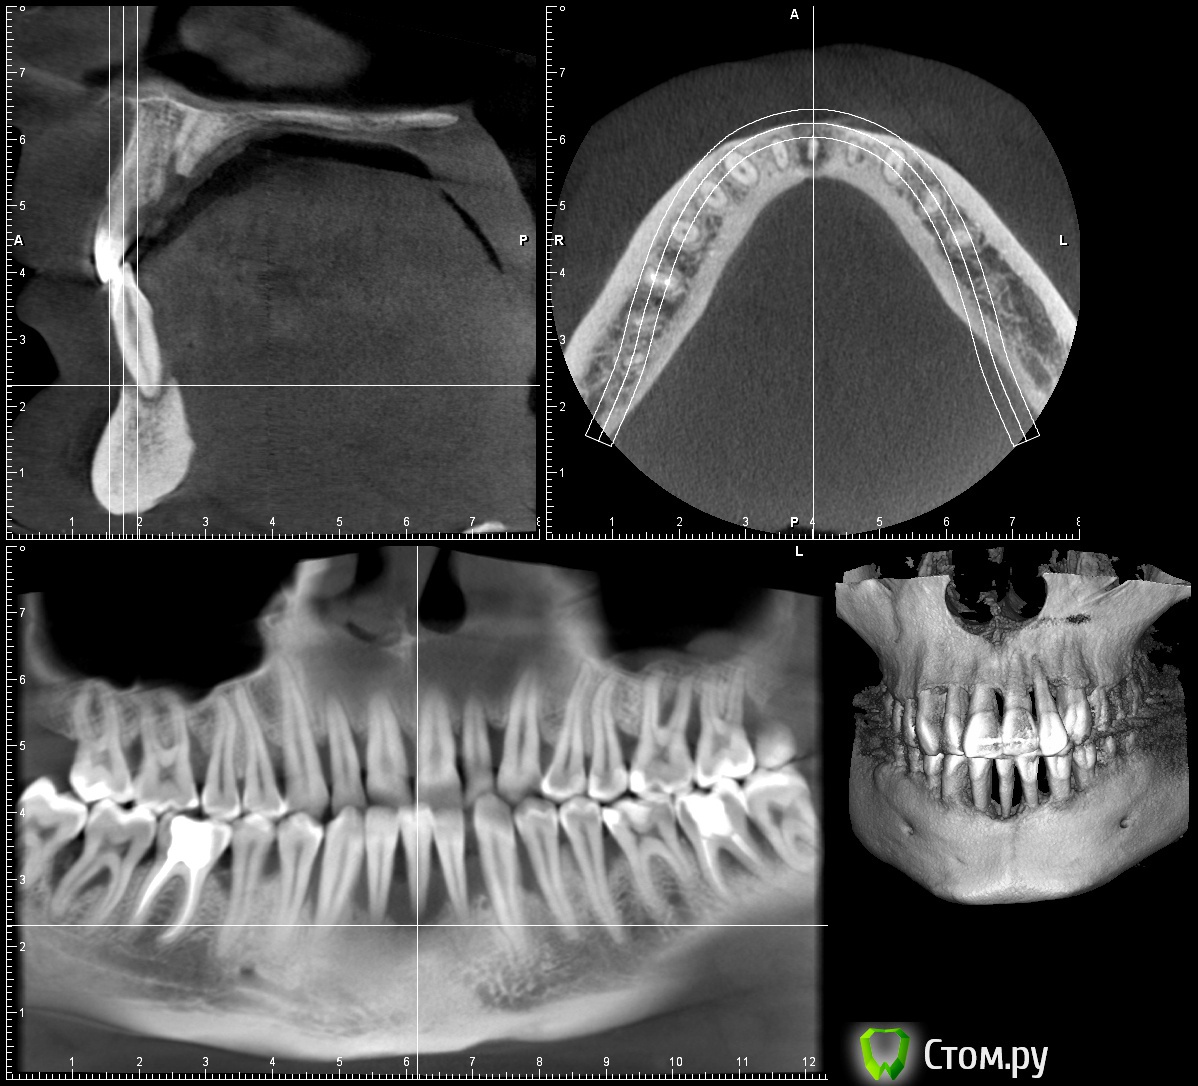

rsavvin Опубликовано 4 января, 2014 Автор Поделиться Опубликовано 4 января, 2014 Привет из Украины, цены тут супер. Сделал томографию. Нижний фронт: доктор сказал, что в плане вертикальной аугментации ловить нечего -"первый тип кости", рекомендует одномоментную имплантацию 2х ICX'ов. Из проблем - говорит, лошадиные зубы, но у меня чтобы это заметить надо отодвинуть нижнюю губу. У меня вопрос, достаточно ли кости для одномоментной имплантации? Не заденет нерв? Ссылка на комментарий

rsavvin Опубликовано 4 января, 2014 Автор Поделиться Опубликовано 4 января, 2014 Задайте вопрос Вашему Врачу...Если врач рекомендует делать именно так, наверное, нет смысла его переспрашивать. Я потому тут и срашиваю, что хочется услышать аргументированное мнение других врачей, типа согласен, потому что... Или не стоит этого делать, так как... Ссылка на комментарий